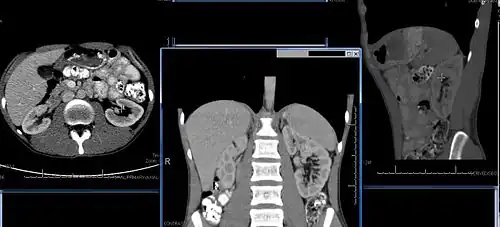

Imaging

Renal ultrasonography is essential in the diagnosis and management of kidney-related diseases.[49] Other modalities, such as CT and MRI, should always be considered as supplementary imaging modalities in the assessment of renal disease.[49]

Chronic kidney disease (CKD) has been recognized as a leading public health problem worldwide. The global estimated prevalence of CKD is 13.4%, and patients with kidney failure needing renal replacement therapy are estimated between 5 and 7 million.[6] Procedures used in the management of kidney disease include chemical and microscopic examination of the urine (urinalysis), measurement of kidney function by calculating the estimated glomerular filtration rate (eGFR) using the serum creatinine; and kidney biopsy and CT scan to evaluate for abnormal anatomy. Dialysis and kidney transplantation are used to treat kidney failure; one (or both sequentially) of these are almost always used when renal function drops below 15%. Nephrectomy is frequently used to cure renal cell carcinoma.